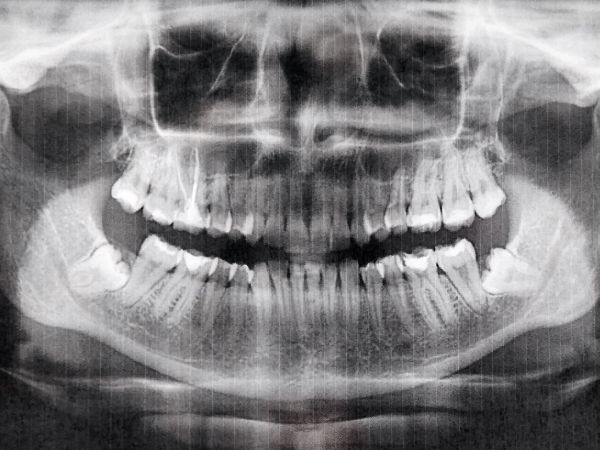

2. Radiografías: Para obtener una visión más profunda, se pueden tomar radiografías que revelen la estructura interna de tus dientes, raíces y huesos maxilares.